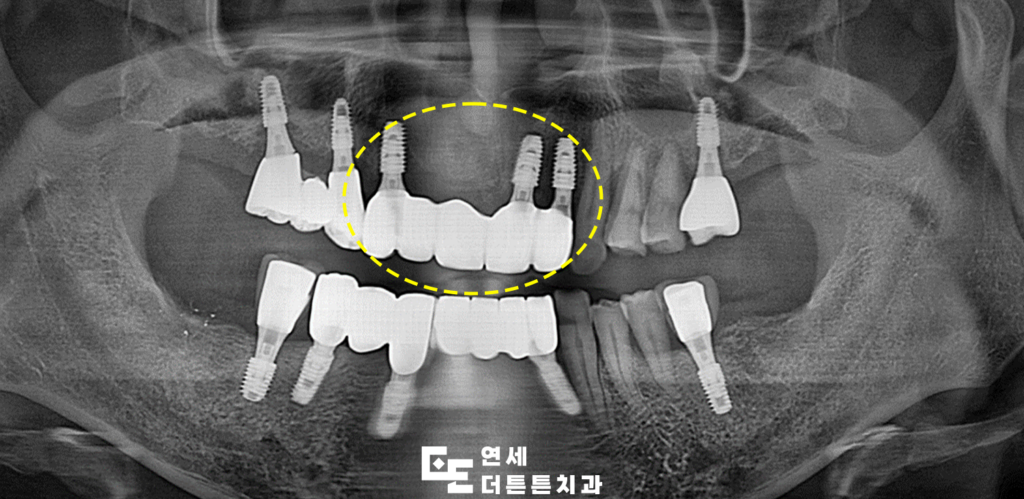

겉으로 보기에는 문제가 없는 듯 보였으나

파노라마를 촬영해 보니, 지탱하고 있던 양쪽

지대치 뿌리 쪽 염증으로 인해 잇몸뼈가 거의

남아 있지 않을 만큼 녹아 있었고

살려 쓰기에는 무리가 있다고 판단되어

발치 후 임플란트 식립 계획을 수립하였습니다.